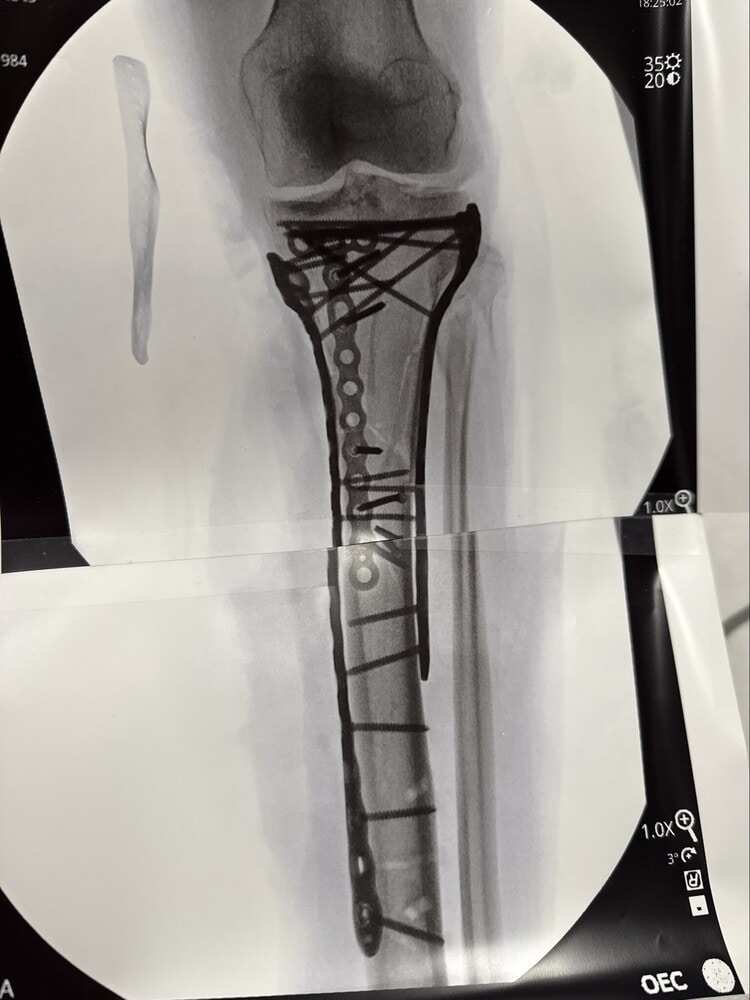

NEW YORK (Stati Uniti) - Lindsey Vonn ancora sotto i ferri. Rientrata negli Usa dopo la caduta nella discesa olimpica dello scorso 8 febbraio a Cortina dove aveva rimediato una frattura complessa della tibia sinistra, la 41enne statunitense si è sottoposta a un'ulteriore operazione. Lindsey si è aperta su X: "Solo un rapido aggiornamento il mio ultimo intervento è andato bene. È durato poco più di 6 ore. Mi sto riprendendo dall'operazione, ma il dolore è stato difficile da gestire. Sto facendo progressi lentamente e spero di poter uscire presto dall'ospedale. Grazie a tutti per il supporto". Appena ripresa dall'intervento, sempre su X, la leggenda statunitense ha pubblicato la lastra della gamba martoriata scrivendo: "Sono bionica per davvero".

La Vonn, rimasta ricoverata per una settimana all'ospedale Ca'Foncello di Treviso dopo la caduta, durante il ricovero in Italia si era già sottoposta a quattro interventi. La campionessa olimpica di discesa a Vancouver 2010 aveva scelto ugualmente di prendere parte ai Giochi Invernali di Milano-Cortina nonostante la lesione del crociato anteriore al ginocchio sinistro rimediata lo scorso 30 gennaio a Crans Montana.